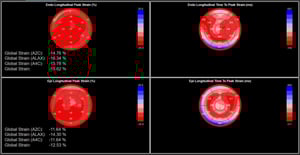

El strain longitudinal global (GLS) mide el acortamiento de las fibras miocárdicas en el eje longitudinal, desde el ápex hacia la base. Este parámetro refleja principalmente la función de las fibras subendocárdicas, que son las más susceptibles al daño precoz.

El GLS permite identificar deterioro funcional en etapas tempranas, incluso cuando la FEVI aún se conserva dentro de valores normales.

Strain radial: complemento funcional

El strain radial evalúa el engrosamiento del miocardio hacia el centro del ventrículo durante la contracción. A diferencia del strain longitudinal, presenta mayor variabilidad y dependencia de la calidad de imagen, lo que limita su reproducibilidad.